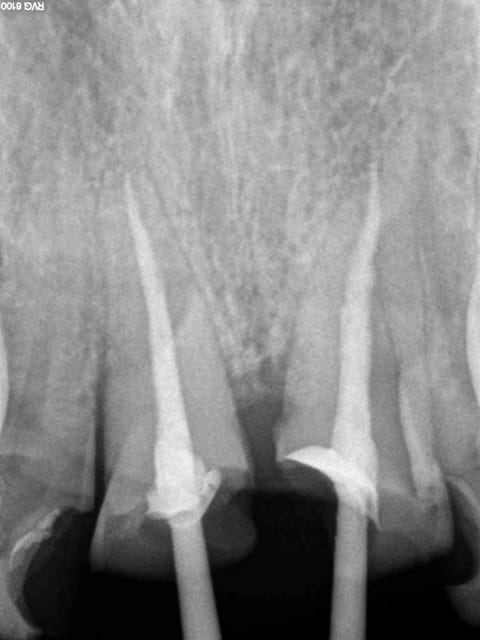

1 sptqqv - Eugenol

2 nrsxww - Eugenol

3 bfr6il - Eugenol

4 yt2f3q - Eugenol

5 rrqwkd - Eugenol

6 nvk9i8 - Eugenol

7 dpigl1 - Eugenol

8 z4bnp9 - Eugenol

9 ad2u4i - Eugenol

10 tgnepm - Eugenol

11 kxxmfo - Eugenol

Endos sans digue, avec de la carie résiduelle, la gutta/ciment ne remplit pas toute la lumière du canal, pas de respect de l'espace biologique, effet férule minimaliste.....

Vu les autres dents le patient ne mérite peut être pas mieux et l'indication est là mieux posée, mais tu te positionnes comme un pro de l'endo puisque tu en ferais souvent et là, c'est pas flagrant...